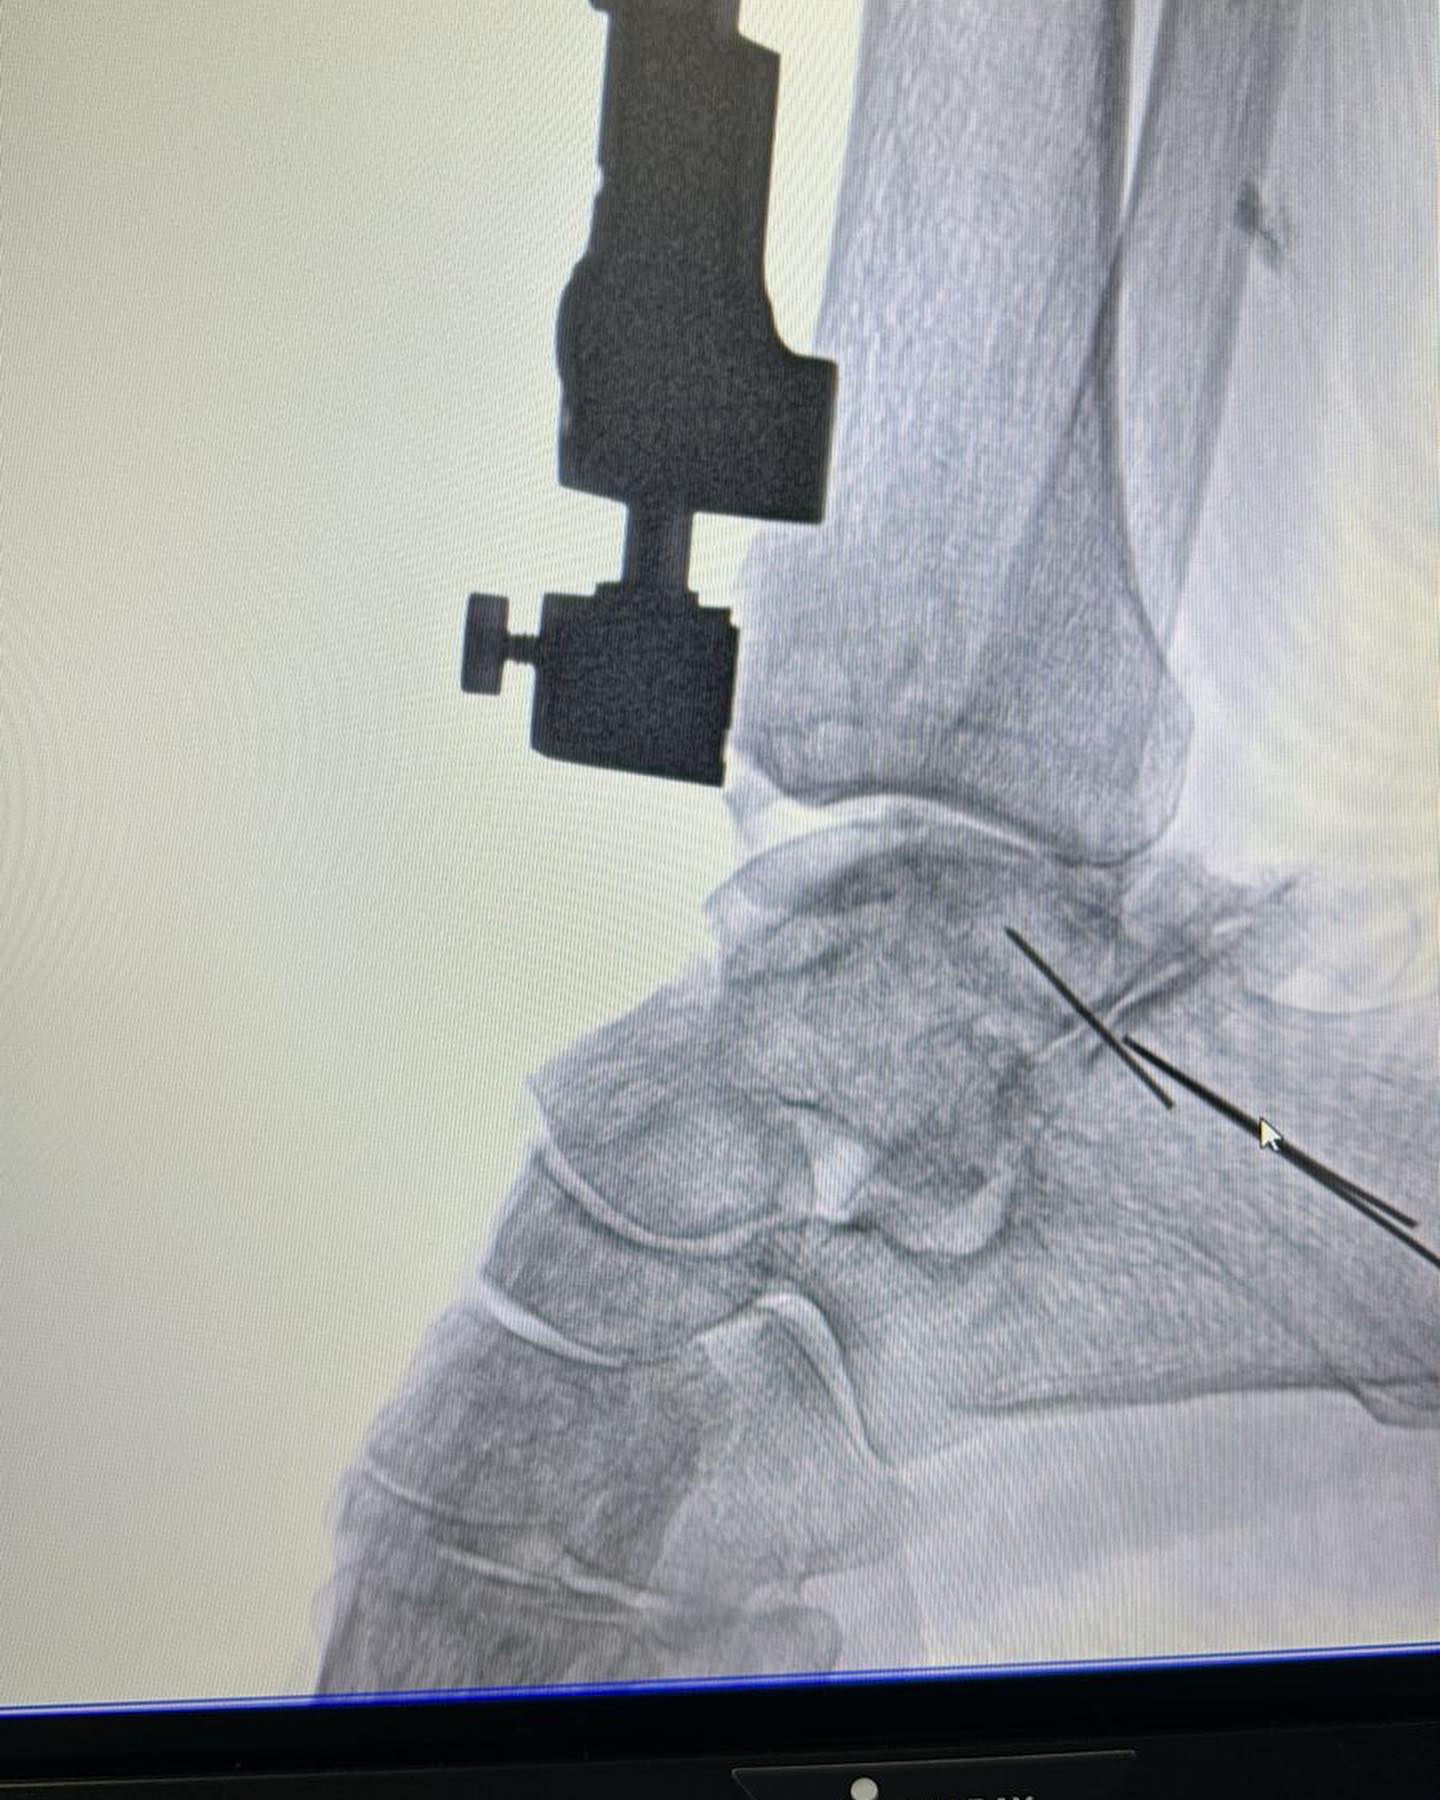

Este procedimiento quirúrgico consiste en sustituir la articulación dañada por una prótesis compuesta de metal y plástico, diseñada para restaurar la movilidad y aliviar el dolor.